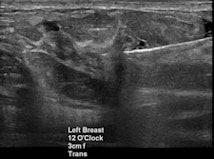

Mammography, ultrasound, and MRI each has its role in diagnosing suspicious lesions. But establishing the radiologic-pathologic correlation is just as important to ensure concordance -- and even that's not necessarily the end of the line for radiologists looking for optimal care, said Shaheen, who is acting chair of radiology and chief of women's imaging at Mafraq Hospital in Abu Dhabi, United Arab Emirates.

"We as the breast imagers are the major players in the multidisciplinary team in breast cancer management, or breast cancer in general, especially if the patient needs some imaging," Shaheen said. "We are consultants to clinicians to advise on what's the next best step, and we are experts on multimodality imaging and interventions including mammography, ultrasound elastography, MRI, core biopsy for fine-needle aspiration, and needle localization."

Breast cancer findings include masses, calcifications, developing asymmetry, and skin thickening, which is often imperceptible, Shaheen said. For whatever reason the patient is called back -- a finding on mammography, a clinical finding, or a patient discovering a symptom -- the diagnostic path generally begins with multimodality imaging, followed by image-guided biopsy. Then comes the critical rad-path correlation and, ultimately, assessment of cancer pathology and hormonal status before deciding on treatment, which greatly depends on the individual case.